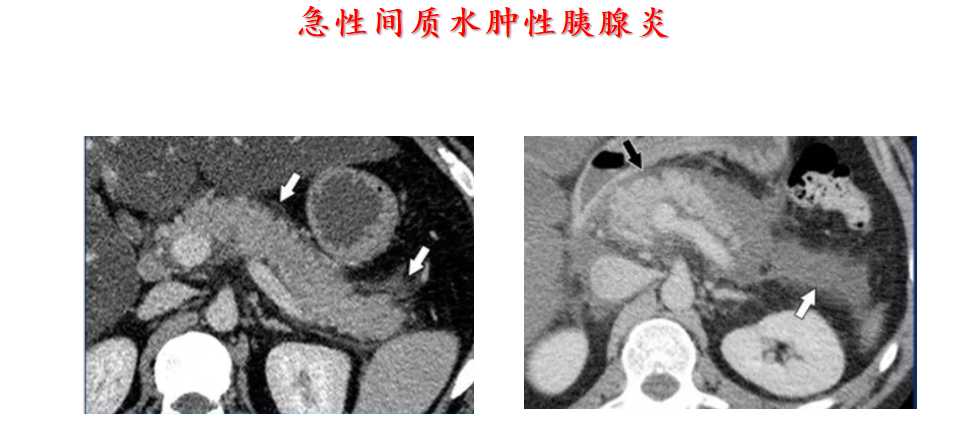

CT:通常诊断准确性高于超声。对于有发热、非区域性(non- localized)腹痛、近期无手术史的患者推荐增强CT;